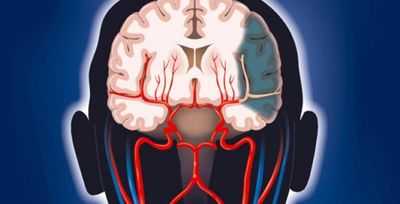

Виллизиев круг: анатомия, варианты развития, патология

Виллизиев круг в мозговой сосудистой системе был описан более трехсот лет назад английским врачом Т. Уиллисом. Строение этого артериального кольца играет большое значение в условиях неблагополучия, когда определенные отделы нервной ткани испытывают недостаточный приток артериальной крови по причине закупорки или стеноза артерий. В норме даже при аномально развитых сосудах этого круга человек не ощущает имеющихся особенностей ввиду полноценности функционирования других артерий.

Строение Виллизиева круга

Классический Виллизиев круг образуют:

- Начальные отделы передних мозговых артерий (ПМА);

- Передняя соединительная артерия (ПСА);

- Задние мозговые артерии (ЗМА);

- Задние соединительные артерии (ЗСА);

- Надклиновидная часть внутренней сонной артерии (ВСА).

Перечисленные сосуды формируют подобие семиугольника. ВСА приносят кровь к мозгу из общих сонных и на основании мозга отдают ПМА, которые сообщаются друг с другом посредством ПСА. Задние мозговые артерии начинаются от основной, образующейся путем объединения двух позвоночных. Между ВСА и ЗМА есть связь — задние соединительные сосуды, в зависимости от диаметра получающие питание либо из системы внутренней сонной, либо из базилярной артерии.

Таким образом, образуется кольцо, связывающее два артериальных потока — из бассейна внутренней сонной и базилярной артерий, разные части которого могут взять на себя функцию обеспечения питанием тех частей мозга, которые испытывают недостаток крови при закупорке или сужении других составляющих мозговой сети.

Виллизиев круг находится в подпаутинном пространстве основания головного мозга, окружая своими составными элементами зрительную хиазму и образования среднего мозга, позади находится Варолиев мост, на поверхности которого расположена базилярная артерия.